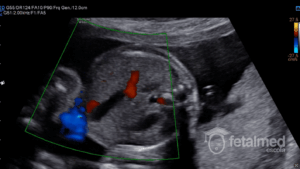

Apesar do conceito fisiopatológico da Restrição de Crescimento Intra-Uterino e do Feto Pequeno para a Idade Gestacional serem bastante distintos, a diferenciação entre estas duas situação é extremamente desafiadora na prática diária. Ao ultrassom, o estudo dopplerfluxométrico tem sido utilizado para fazer essa diferenciação uma vez que a insuficiência placentária está associada a alterações de fluxo placentário e fetal.

Em 2014 Figueras e Gratacós propuseram uma classificação para os casos de restrição de crescimento intra-uterino baseada em um estadiamento progressivo. Uma vez que um feto pequeno é identificado (isto é, seu peso estimado está abaixo do 10º percentil), um estudo dopplerfluxométrico deve ser realizado. Os vasos a serem investigados são as artérias uterinas, a artéria umbilical, a artéria cerebral média devendo-se calcular a relação cérebro-placentária. Nos fetos com alteração na artéria umbilical, o ducto venoso e a cardiotocografia computadorizada devem ser realizados quando estiverem disponíveis. Abaixo você encontra o estadiamento proposto e também poderá usar a nossa Calculadora de Doppler para estadiamento dos casos de restrição de crescimento intra-uterino.